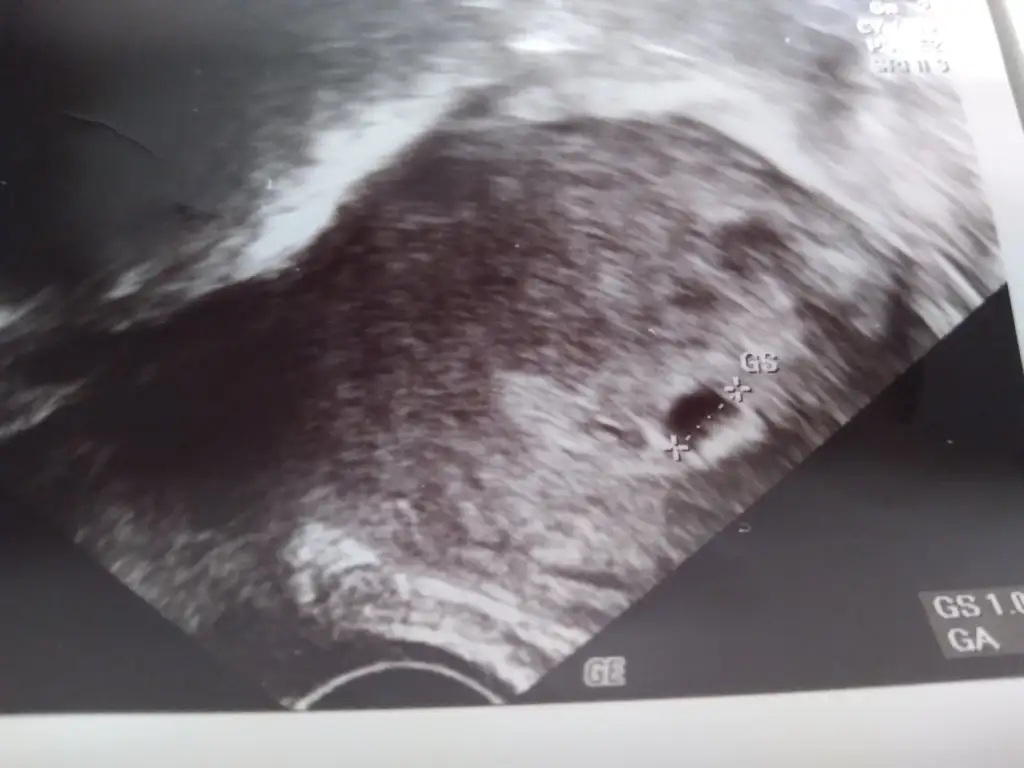

Normalde transfer tarihine göre 6 haftalık olması gerekiyor. Ultrasonda kese göründü ben şok oldummmmm.5 hafta 1 günlük görünüyor ama bu sıkıntılı bir durum değil çok karşılaşıyoruz 1 hafta geriden gelmesine dedi doktor. İnşallah sağlıkla ilerler dedi. 2 hafta sonra kontrole çağırdı.Eki Görüntüle 3129834

1 cm dedi yanlış hatırlamıyorsam 5 hafta 1 günlük dedi.Kesenin boyutunu söyledimii

Aaa kesen baya iyi benimki gecen perşembe 3,5mm di inşallah benimkide büyümüştür sağlıkla1 cm dedi yanlış hatırlamıyorsam 5 hafta 1 günlük dedi.

Kesenin boyutu ultrasonun üstünde mi yazıyorAaa kesen baya iyi benimki gecen perşembe 3,5mm di inşallah benimkide büyümüştür sağlıkla